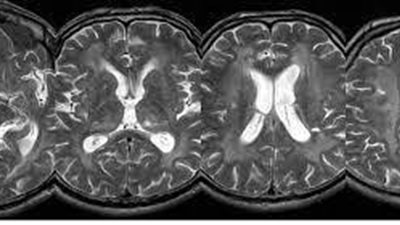

باحثون يحددون العلامات التحذيرية المبكرة لفقدان البصر بسبب اضطراب الدماغ

يصيب 1 من كل 40 ألف طفل.. تعرف على حثل المادة البيضاء